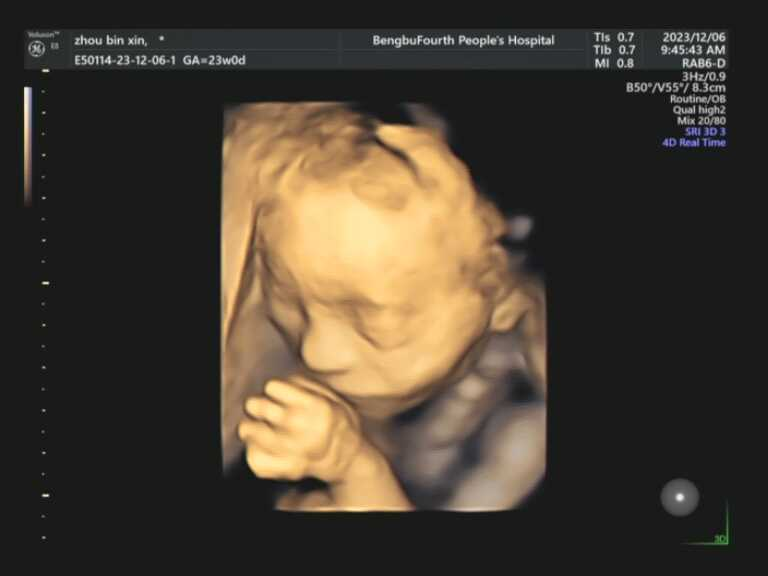

什么时间阶段适合做四维彩超?

孕22-24周,是做四维彩超的最佳时间段。因为这段时间胎儿的各项器官已经基本发育完全,且羊水较多,更加容易观察胎儿的生长发育状况,孕妈妈们一定要提前预约。